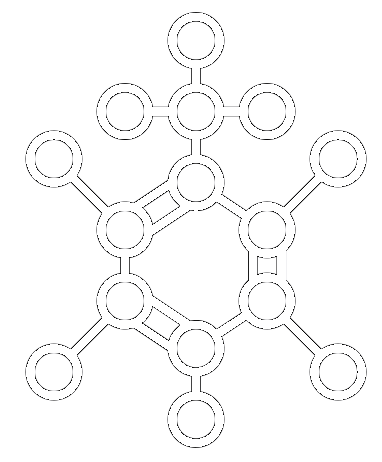

TOLUENE